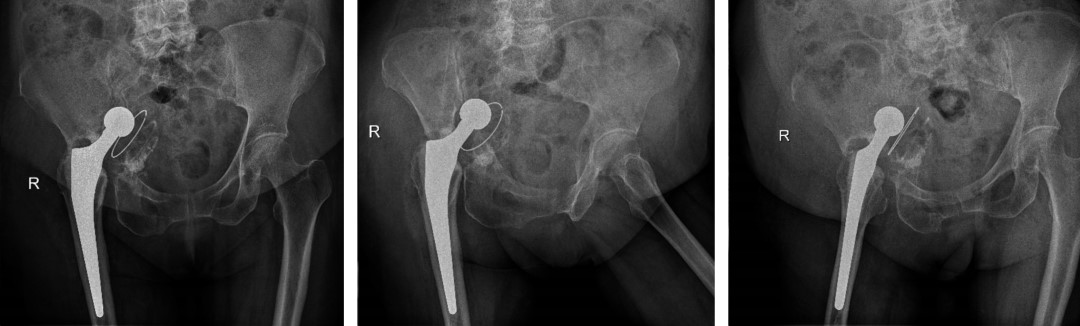

Femenino de 82 años. Sin antecedentes clínicos de importancia, salvo por una artroplastía total de cadera derecha cementada hace un mes. Acude por dolor en cadera derecha e incapacidad a la deambulación. La paciente refiere dolor en cadera derecha que limita realizar fisioterapia y no tolera bipedestación ni sedestación. Examen físico: paciente no deambula. Miembro inferior derecho: cadera: presencia de herida cicatrizada de aproximadamente 12 cm. Rangos de movilidad no valorables por dolor, limitados. Acortamiento clínico de 1 cm neurovascular distal conservado. Harris Hip Score (HHS) de 16 puntos y escala visual análoga (EVA) de 8/10. Se solicitaron estudios radiográficos complementarios (Figura 1).

Figura 1